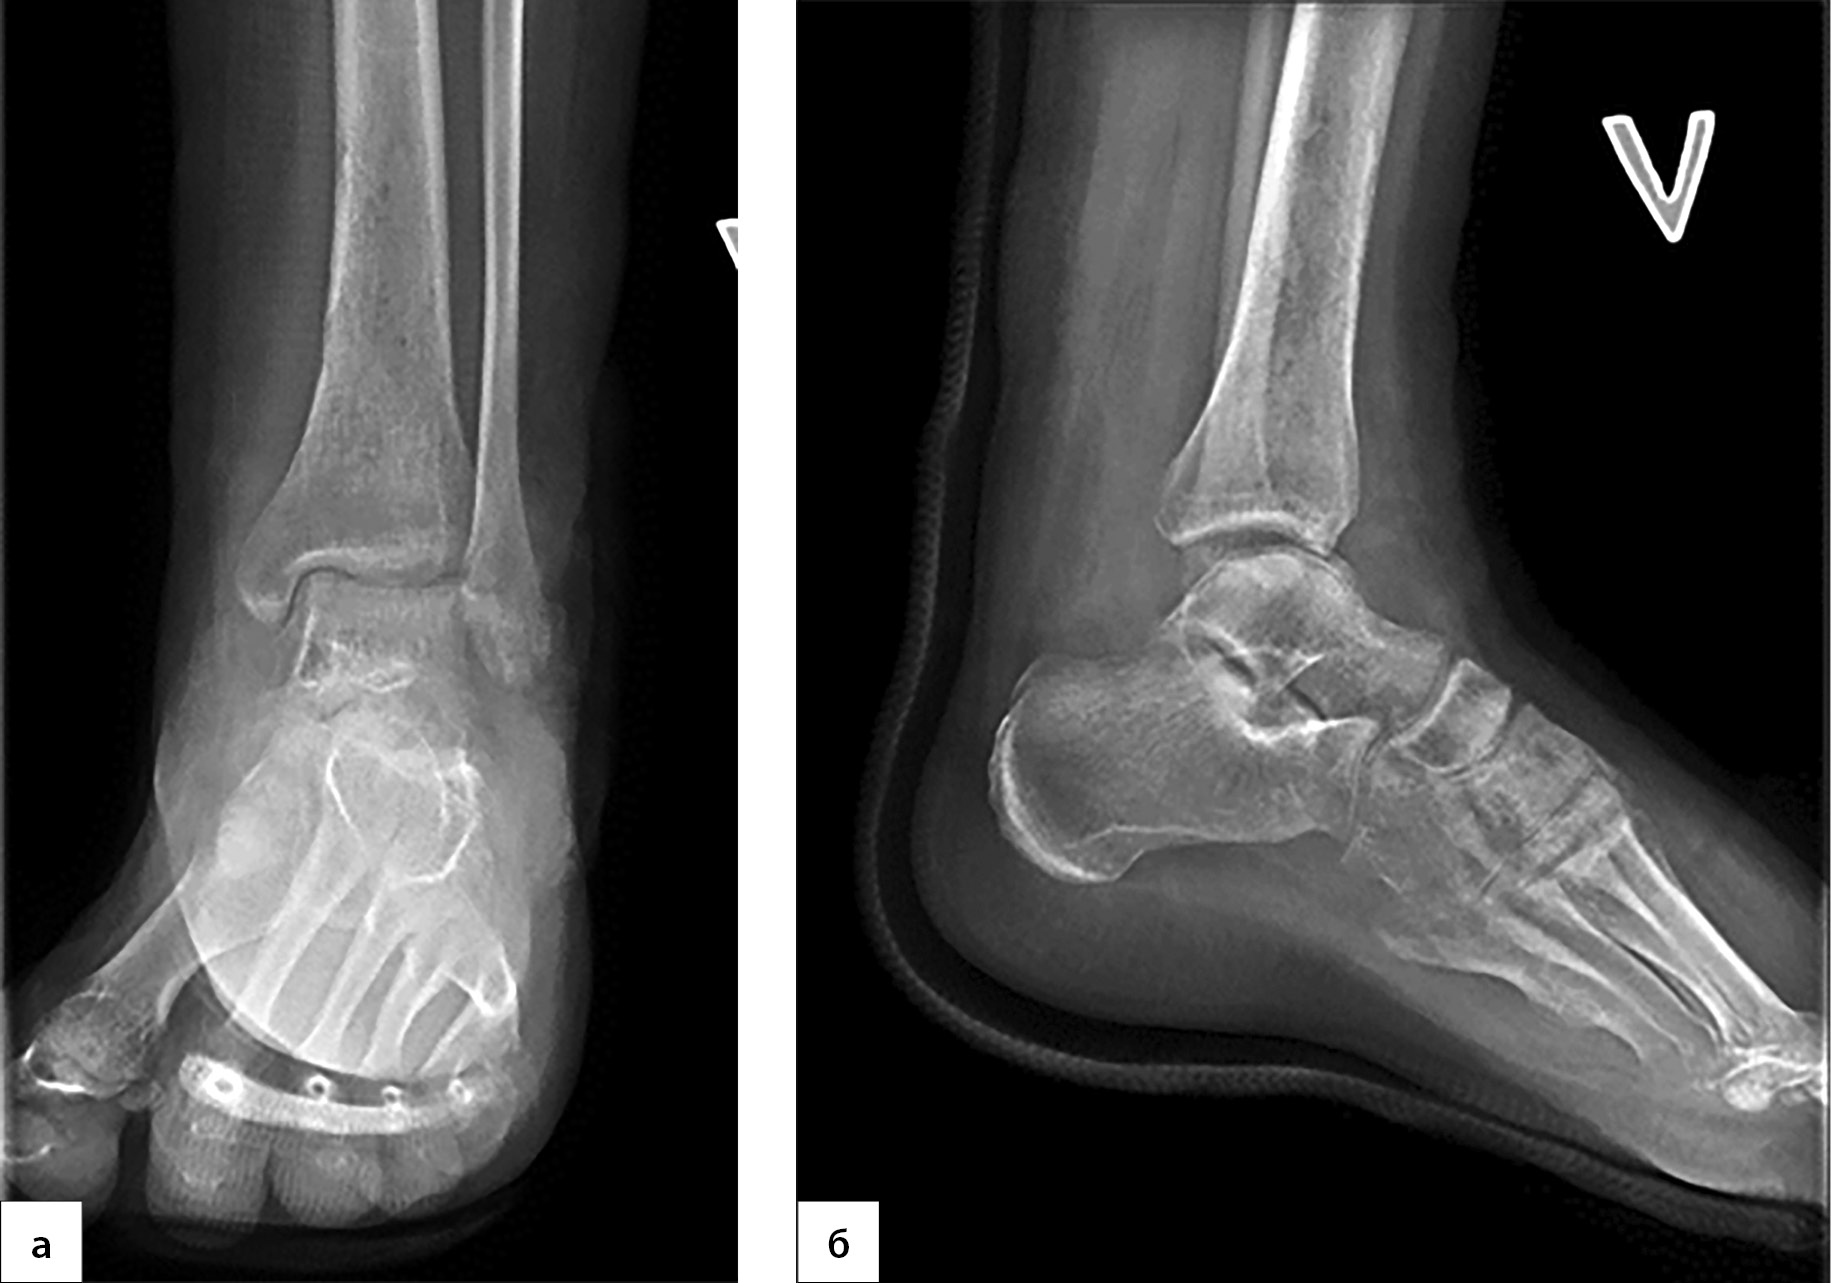

1. Рисунок 1. Рентгенография левого голеностопного сустава и стопы на догоспитальном этапе. (а) — прямая проекция; (б) — боковая проекция) | |